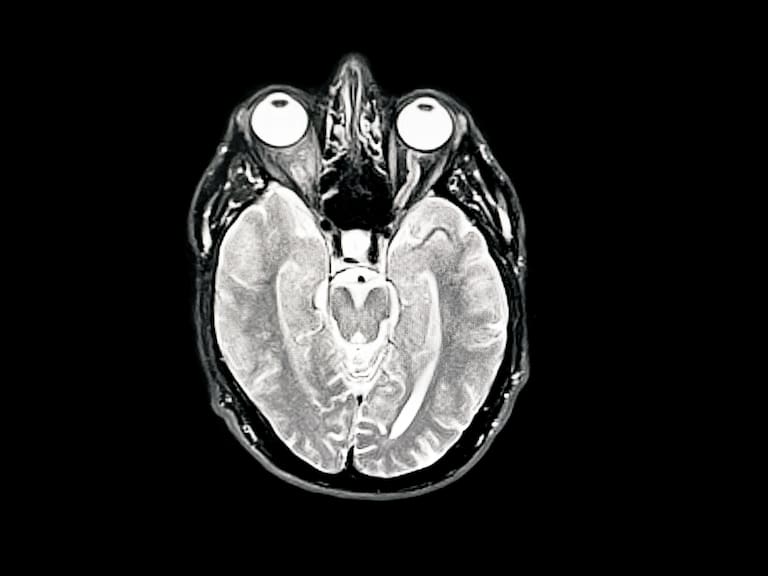

Un estudio internacional de largo plazo sugiere que un tipo específico de entrenamiento cognitivo, centrado en la velocidad de procesamiento y la atención, podría reducir el riesgo de ser diagnosticado con Alzheimer y otras demencias en personas mayores.

La investigación analizó datos del estudio ACTIVE, un ensayo clínico aleatorizado iniciado a fines de los años 90 en Estados Unidos, que siguió a más de 2.000 adultos mayores de 65 años durante dos décadas, vinculando su participación en programas de entrenamiento cognitivo con registros reales de diagnósticos médicos de Medicare.